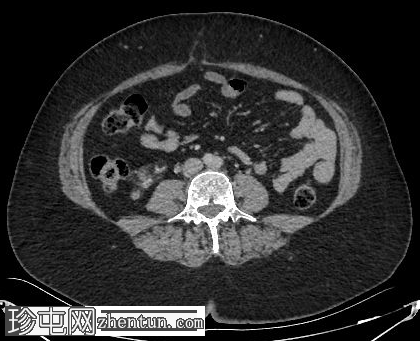

轴位

平扫

肝脏内可见多发边界清晰的脂肪结节状病变,最大病变位于肝脏VII段,直径15 mm

双肾可见多发脂肪肿块,右肾最大病变直径达45 mm,左肾最大病变直径20 mm

椎体可见小的硬化性骨病变